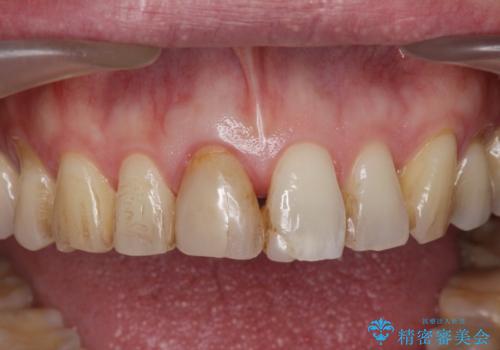

- 前歯の変色が気になり審美障害の改善を求めて来院されました。

根管治療に伴う歯の色調変化はよく見られる所見です。

セラミッククラウン製作を行い審美性の改善を計画します。